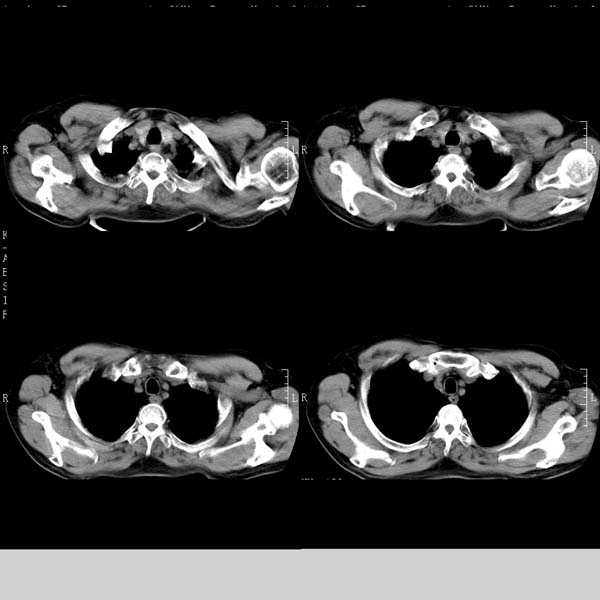

以下是引用守望可可西里在2008-6-24 1:11:00的发言:[br][br] 考虑为周围型肺癌:[br] 1.分叶结节,形态极不规则,蟹足样伸展的恶性浸润特征比较明确。[br] 2.磨玻璃影中由多个更高密度小结节聚集呈梅花瓣样。[br] 3.局部胸膜凹陷征比较明确。[br][br] 另:纵隔胸膜明显增厚、粘连。

以下是引用zjzjr在2008-6-24 11:19:00的发言:[br]支持左下肺周围型肺癌伴右肺转移,纵隔淋巴结转移,心包积液.

以下是引用zhangling在2008-6-24 14:56:00的发言:[br]我们科室意见报告为[br][br]1考虑左下肺周围型肺癌[br]2右肺小结节考虑转移瘤,纵隔淋巴结转移[br]3心包积液. [br] 各位老师分析的相当好 谢意[br]